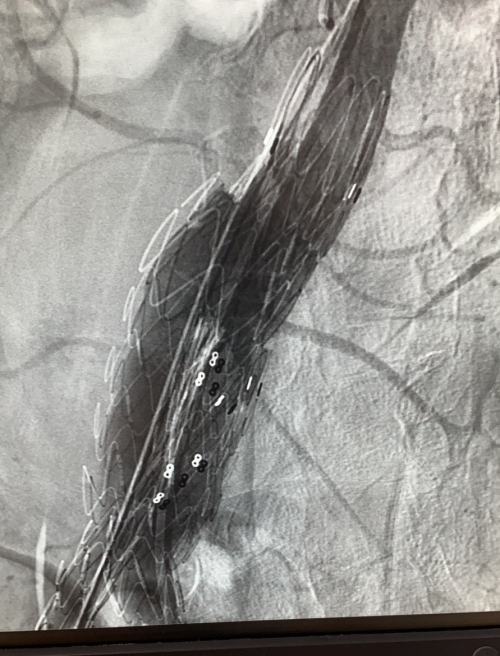

术后造影

8月11日,欧阳长生为陈先生开展介入治疗,在DSA透视下反复确认支架主体释放位置后逐步释放支架系统,待左侧髂支完全释放后,再次经右侧髂动脉鞘管送入髂支分支支架,并精准于主动脉支架主体髂支衔接后稳定释放,最终实现主动脉瘤体的完全隔绝。术后造影显示瘤体完全封闭,双侧肾动脉及髂动脉血流未受到影响,手术顺利。因肾动脉血流未受影响,进一步提升了患者的生存质量。